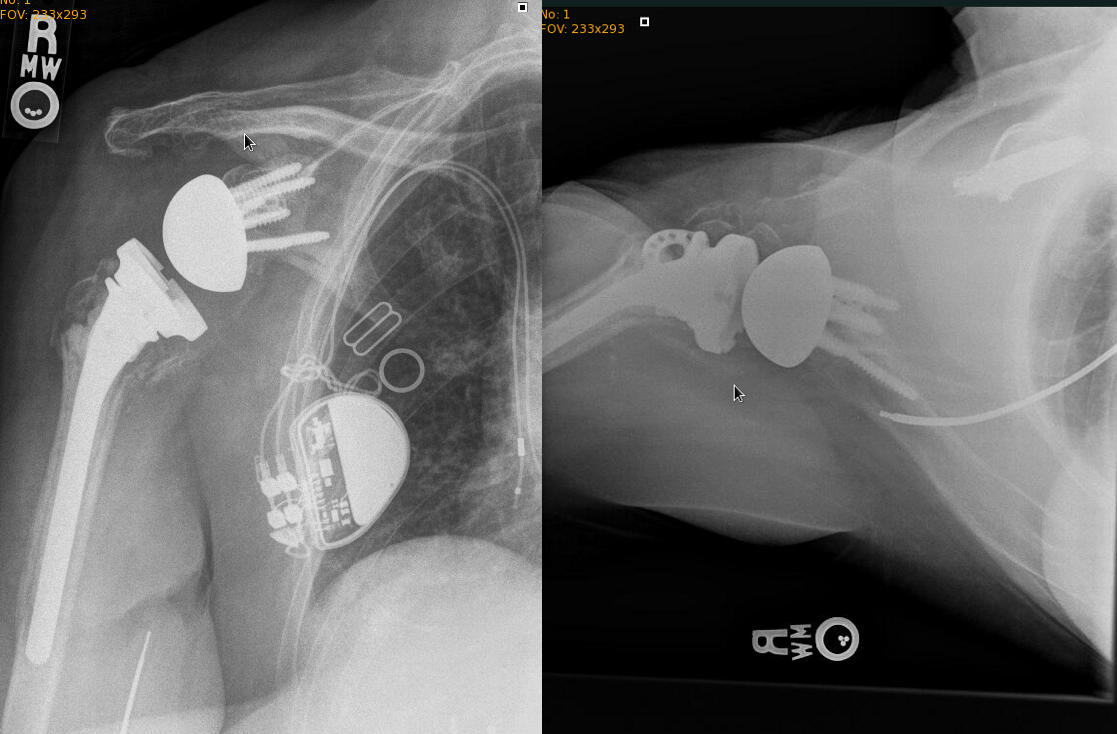

On the left is the pre-surgery appearance of the left shoulder. Note the new distal location of the humerus compared to the situtation before surgery.

This patient initially elected to not have surgery. Approximately 3 weeks later she reevaluated her situation and sought surgical treatment due to continued severe pain. The reverse shoulder replacement was done over 1 month after the injury.

Reverse shoulder replacement resulted in quick improvement.

Range of motion after reverse replacement is expected to be less than the full natural range of motion of the shoulder joint. This patient was able to raise the arm above the shoulder level. She became able to wash her face, comb her hair, and feed herself within 1 month. She was able to drive 6 weeks after surgery.

This is the xray appearance approximately 2 years later.